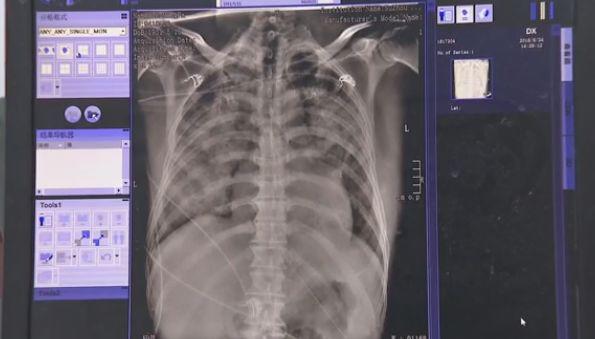

Cả 2 phổi của ông Lưu đều bị hoen ố.

Theo tìm hiểu của bác sĩ, người bệnh là ông Lưu, 50 tuổi. Sau khi kiểm tra cho ông Lưu, bác sĩ phát hiện, bệnh nhân có nhiều cơ quan bị suy yếu, các chỉ số gan, thận có những bất thường nghiêm trọng, đến ngày thứ hai sau khi nhập viện ông Lưu đã tử vong. Cả 2 lá phổi đều đã bị bạc trắng vì phù phổi, lượng lớn chất lỏng đã thấm vào phổi, dẫn đến suy hô hấp.